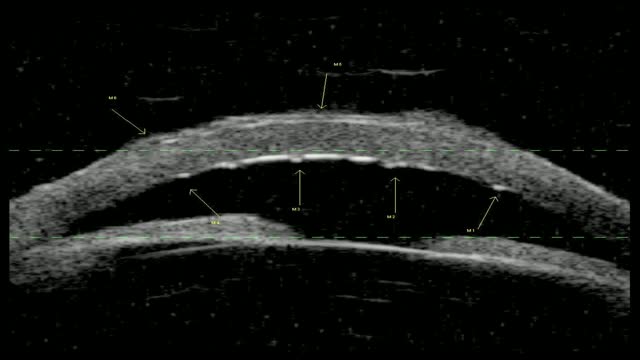

This video demonstrates the use of the Victus femtosecond laser for cataract surgery. Technique for cataract removal with the Stellaris phaco unit is described utilizing the Storz Zero Phaco Hand piece. A six radial cut femto pattern is used.